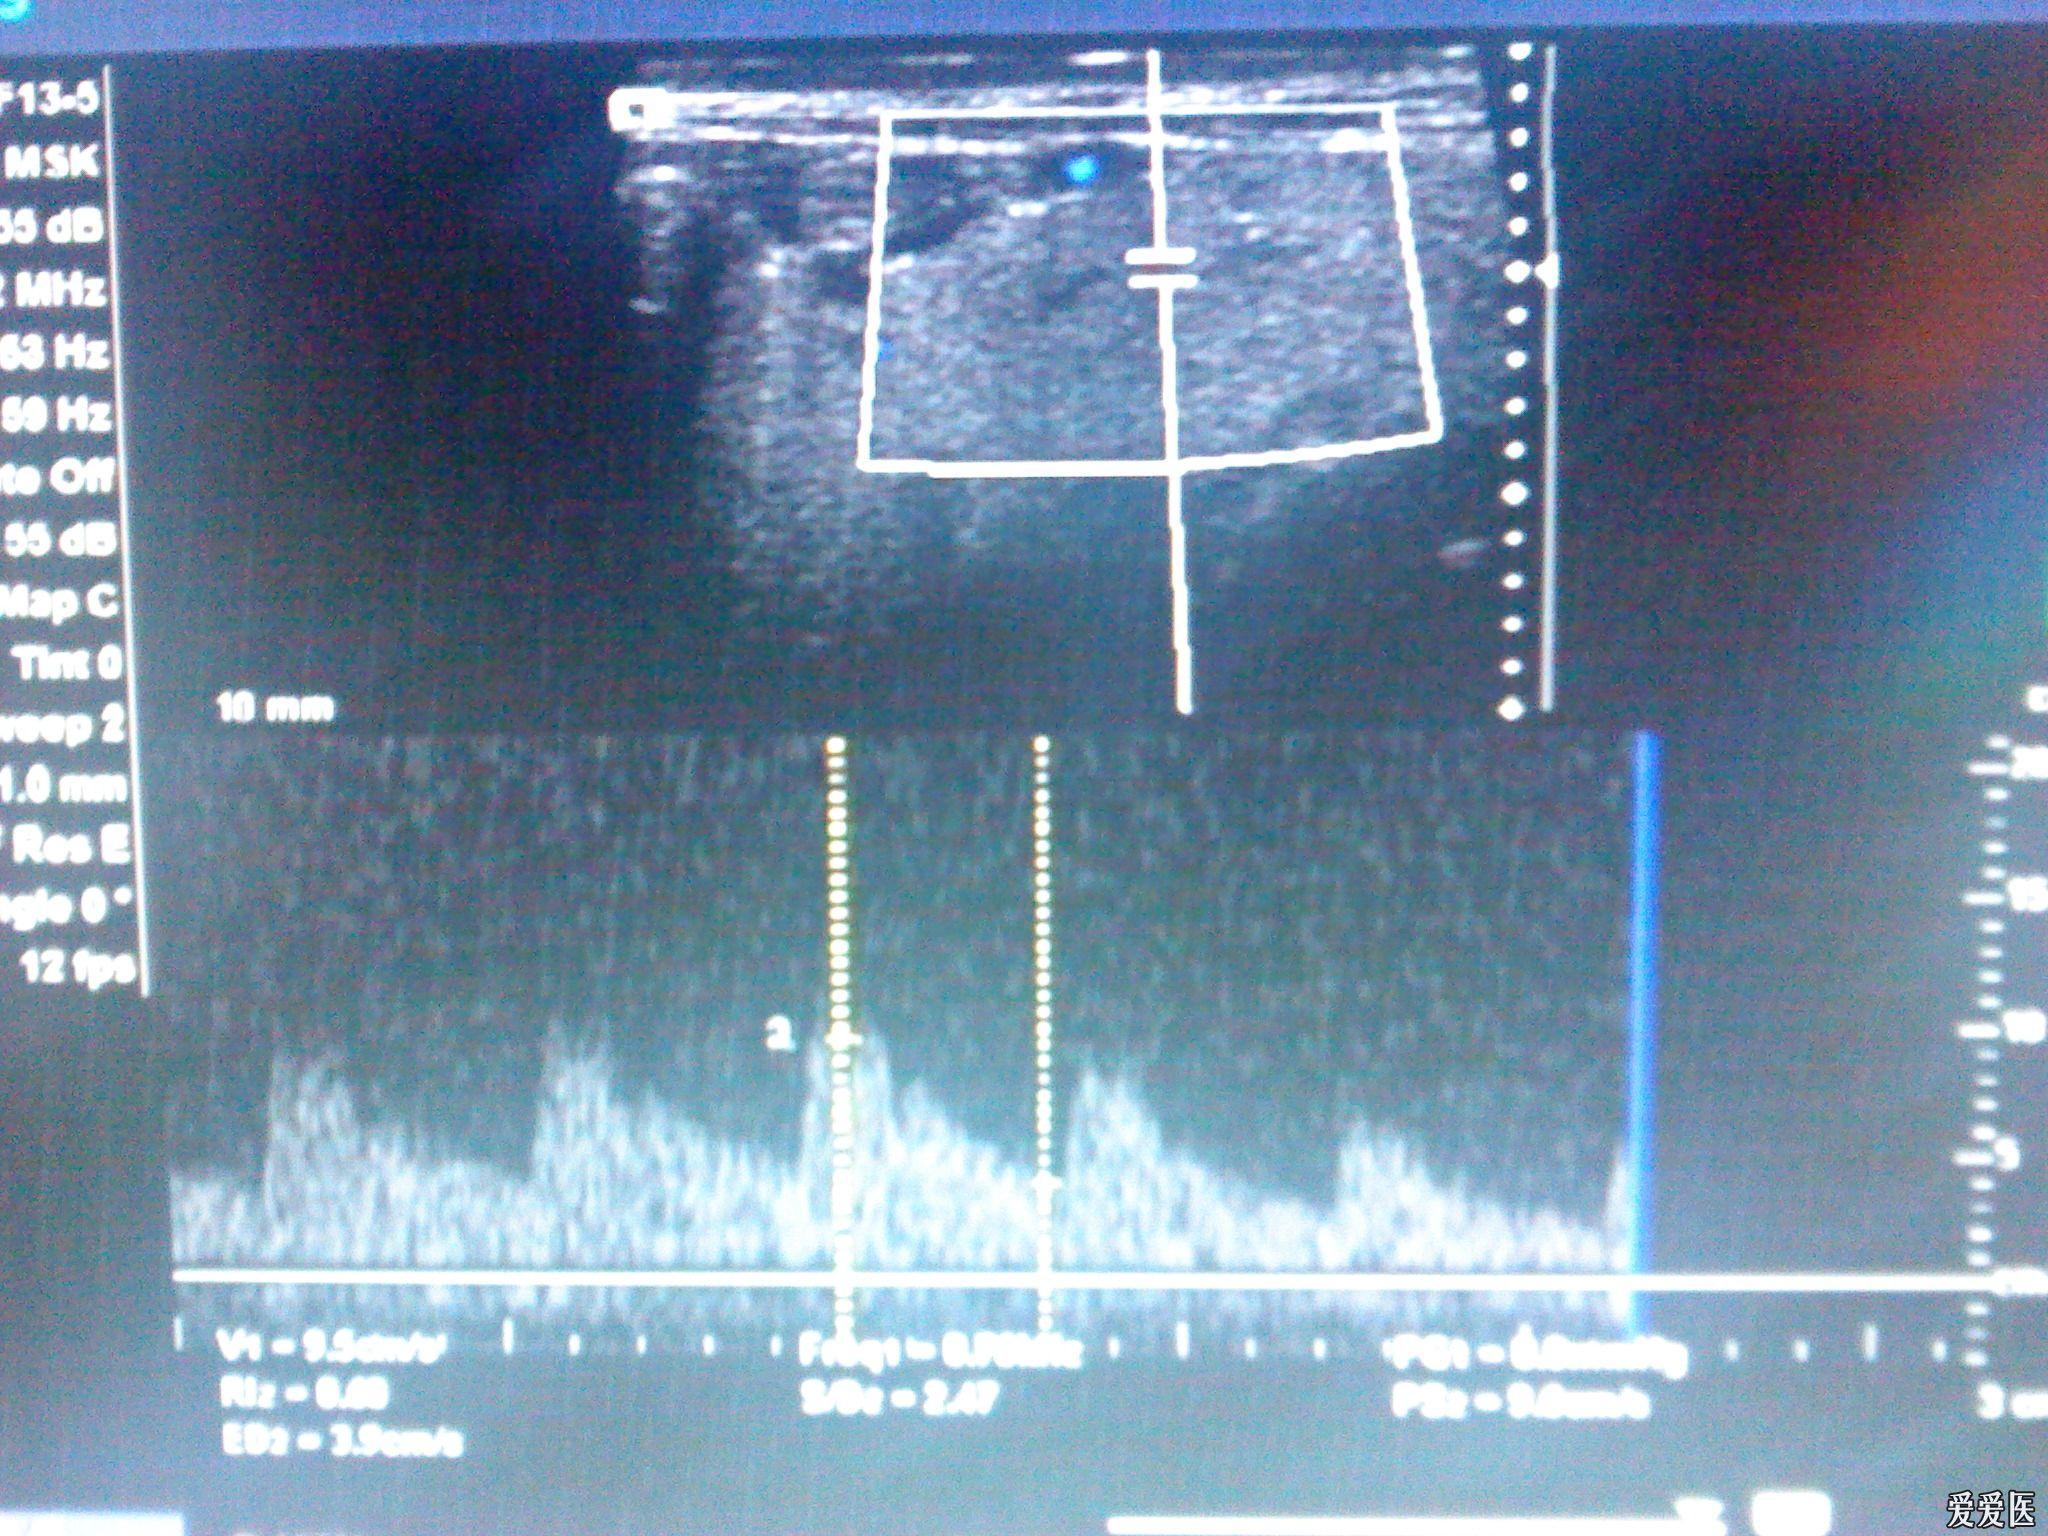

颌下腺炎

图片尺寸2048x1536